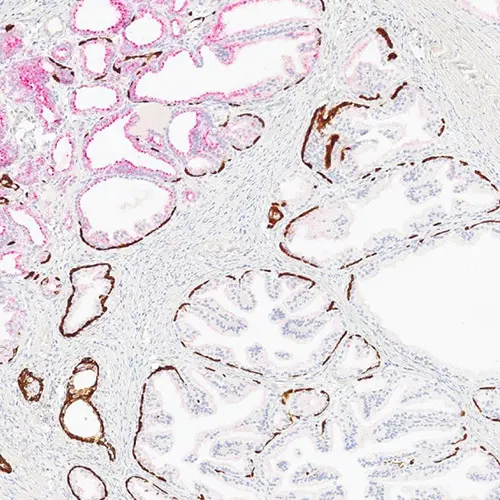

Maximize your efficiency with ChromoPlex 1 Dual Detection for BOND-MAX and BOND-III. ChromoPlex 1 delivers a fully automated, one-step solution for parallel dual-plex staining in immunohistochemistry.

• Stable red and brown chromogens in one detection kit

• Crisp and clear red and brown staining, allowing for excellent ease of interpretation